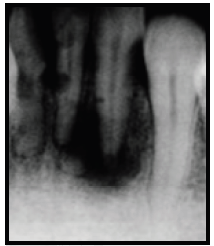

Analise a figura a seguir:

Radiograficamente, pode-se visualizar:

reabsorção óssea devido a bolsa periodontal infra- óssea;

reabsorção inflamatória transitória;

reabsorção inflamatória progressiva;

reabsorção óssea cervical;

reabsorção substitutiva.